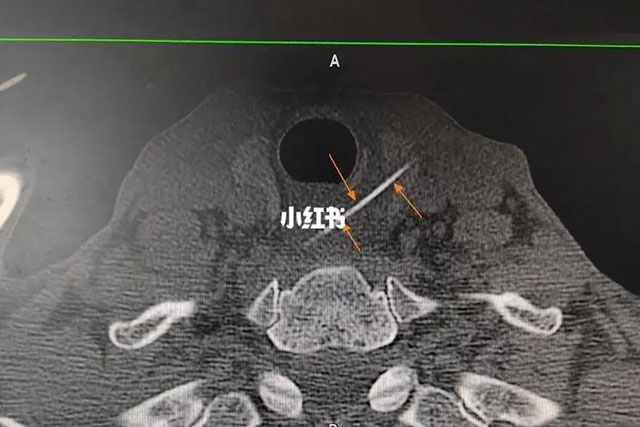

陈光明副教授为李大爷做了颈部CT检查,仔细查看后才发现这根“消失”的鱼刺,已经完全穿透了食管。

陈光明副教授完善术前准备后,立即通过手术取刺。由于鱼刺细小,结合术前颈部CT及彩超定位大致范围,术中再结合彩超精确定位,在李大爷颈部开了一个约2cm长的小口后,将这根长约5cm的鱼刺成功取出。